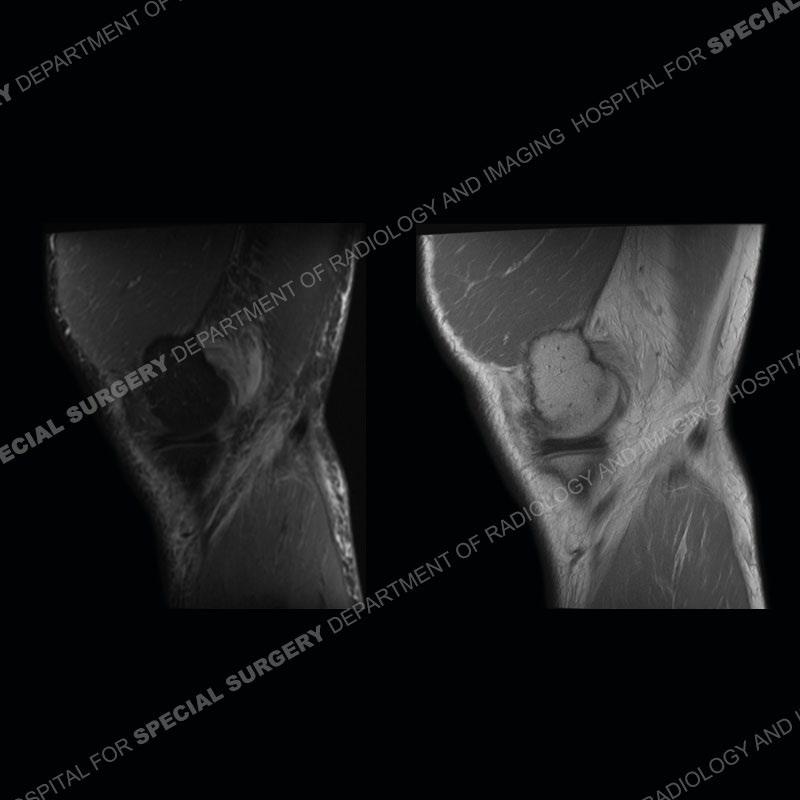

The radiographs show degenerative change of the medial compartment and a varus knee, but they are not germane to this case. No acute bony injury is present. The MRI shows edema of the posterior medial knee/soft tissue and a focal area of a partially disrupted low signal structure. The details are kept at a minimum in the findings of this case on purpose.

The findings were kept purposefully vague as identifying the structures early on takes away a lot of the diagnosis. An uncommon entity and one of which we do not see a lot. Enthesopathic changes and tendinosis are seen as are distal MHG injuries, but proximal tears are rarely present. This case highlights a number of points. One, it almost always comes down to anatomy. Perhaps not a structure we normally spend too much time on, except save for diagnosing a Baker’s cyst, but knowing where this structure and all structures exist in all three planes is imperative. Second, when you think you are making a “call” or finding that you have never made before, step back and think is this just the abnormal presentation of a common pathology. That situation arises much more frequently. Third, if you look at it once, twice, and probably a third time and are confident in your odd or very rare diagnosis, stick to your guns. Especially, when it comes down to anatomic structures, the proof will be in the images.

Fourth, use all imaging planes and different pulse sequences to make your diagnosis. The edema highlighted in this case can be seen as the obscuration of fat on the PD images but is much easier to perceive as the high signal on the IR pulse sequences. The actual disruption of the MHG myotendinous junction is only able to be seen on the axial images. On the sagittal and coronal images, we get a sense something is wrong but hard to be exact. Lastly, when you look at a study and something just seems off (as I would say the sagittal and coronal images do with that dark band of tissue posteriorly), listen to yourself and go through the study slowly and meticulously. Most of the time you will find you were right, and something indeed is present.